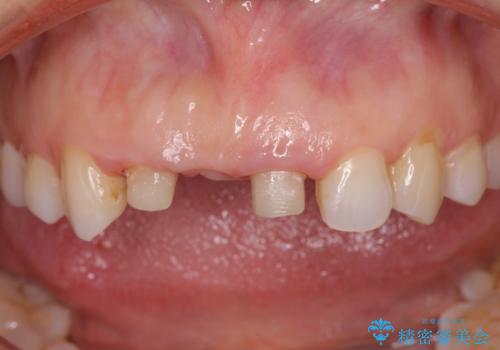

- 前歯のブリッジがすぐに外れる、歯ぐきが腫れている、見た目を良くしたい、と希望され来院されました。

現在装着されているブリッジを除去したところ、歯ぐきよりも上に存在する歯質(縁上歯質)が少なく、土台の形態の悪さや不適合などさまざまな問題があります。